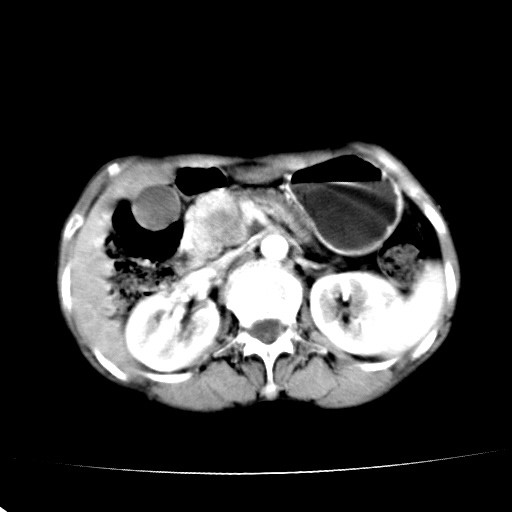

以下是引用jiangjing在2008-6-3 13:36:00的发言:[br]支持 胰头癌------肝内外胆管扩张,胰管扩张,胰头增大,增强见结节状轻度强化影,双管征明显

以下是引用卜一在2008-6-3 14:40:00的发言:[br]支持:胰头癌!(肝内外胆管扩张,胆囊高度扩张,胰管扩张,胰头增大,增强见结节状强化,明显低于胰腺强化密度,并明显见双管征)

以下是引用dyqct在2008-6-3 14:54:00的发言:[br]支持 胰头癌伴肝内外胆管扩张,胰管扩张,胰头增大,增强见结节状轻度强化影,双管征明显。肠系膜上静脉已受侵(已不能手术),建议离子植入治疗吧。